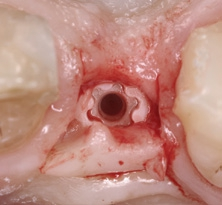

Der chirurgische Eingriff wurde unter Lokalanästhesie mit palatinaler und labialer Infiltration durchgeführt. Zuerst erfolgte die Entfernung des Implantats. Für die Explantation wählten wir das aus unserer Sicht knochenschonendste Verfahren. Mithilfe einer Extraktionszange und mit entsprechend dosierter Kraft drehten wir das teilweise ankylotische Implantat in Achsrichtung aus, um auf jeden Fall die dünne labiale Knochenlamelle zu erhalten (Abb. 3). Dabei frakturierte der osseointegrierte Implantatapex tief im Implantatbett (Abb. 4). Um diesen zu entfernen, musste ein minimalinvasiver apikaler Zugang geschaffen werden. Nach einer krestalen Inzision mit mesialer Tunnelpräparation und distaler Entlastungsinzision sowie der Präparation eines Mukoperiostlappens zeigte sich ein ausgeprägter konkaver Alveolarknochen. Mit einem piezotechnisch unterstützten Chirurgieansatz fenestrierten wir die labiale Knochenlamelle (Abb. 5). Durch diesen minimalinvasiven Zugang lösten wir die ankylotische Verbindung und entfernten den apikalen Implantatrest. Bei dieser Methode der Implantatentfernung wird der periimplantäre krestale Knochen weitestgehend geschont.

Extraoral wurde das explantierte Implantat auf Vollständigkeit geprüft, indem die beiden Teile passgenau aufeinandergelegt wurden (Abb. 6). Nach sorgfältiger Kürettage, intensiver Spülung und Dekontamination der Defektstelle wurde das prothetisch orientierte Implantatlager mit den entsprechenden Formbohrern für das CERALOG Hexalobe Implantat (12 mm L, 4 mm Ø) über den bestehenden Implantatfundus hinaus apikal aufbereitet (Abb. 7). So konnte eine ausreichende Primärstabilität des Implantats erzielt werden. Um einen ausreichenden Knochen-Implantat-Kontakt zu erreichen, musste der Stollen mit einem Gemisch aus autologen Knochenspänen und Bio-Oss Collagen (Geistlich) vor der Insertion augmentiert werden (Abb. 8) [15]. Das Implantat wurde mit dem Eindrehinstrument aus dem Blister genommen und manuell in das Knochenfach inseriert. Das Implantat erreichte eine Primärstabilität von 20 Ncm. Das Design der Innenkonfiguration trägt dem Material Zirkoniumdioxid Rechnung. Die optimierte Hexalobe-Verbindung erlaubt beispielsweise eine höhere Kraftübertragung als eine Sechskantinnenverbindung. Beim Einbringen wird die Kraft radial in das Implantat eingeleitet und Spannungsspitzen werden vermieden.